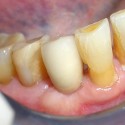

Foto 1: Situazione iniziale: alveolo dopo l’estrazione

Foto 6: Il sorriso finaleIl paziente portava da diversi anni una corona in porcellana sorretta da un perno posto all’interno del canale della radice del 22 (incisivo laterale superiore sinistro).

Un processo carioso a carico della radice non permetteva la stabilità della corona e del suo perno (la corona in porcellana si staccava continuamente).

In questo caso la terapia d’elezione era l’estrazione della radice e l’inserimento di un impianto endosseo. Si è potuto procedere con la tecnica immediata e flapless cioè, estratta la radice viene inserito l’impianto senza tagliare la gengiva per sollevare il lembo di tessuto gengivale.

Tale tecnica, spesse volte, non è aplicabile perché, in mancanza di osso intorno alla radice, occorre rigenerarlo per inserire successivamente l’impianto.